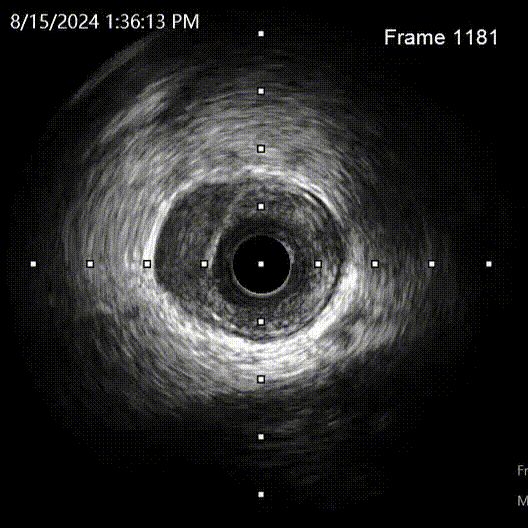

撤出微导管,1.5mm球囊扩张LAD近段后,送入IVUS导管,明确LAD近段导丝是否走行在真腔内,观察LAD在D1分叉处的开口位置,指导CTO导丝的进攻方向。

回撤显示导丝位于真腔,分叉处CTO入口在11-12点处,遂在X线影像中标记入口位置。

再次送入IVUS超声导管至LAD远段回撤,结果显示导丝全程位于真腔,近端见钙化及少量血肿。

IVUS查看见支架远端局部血肿,遂远段植入2.25*29mm支架,并送入2.5*15mm球囊后扩,并用4.0*12mm球囊后扩近段支架。